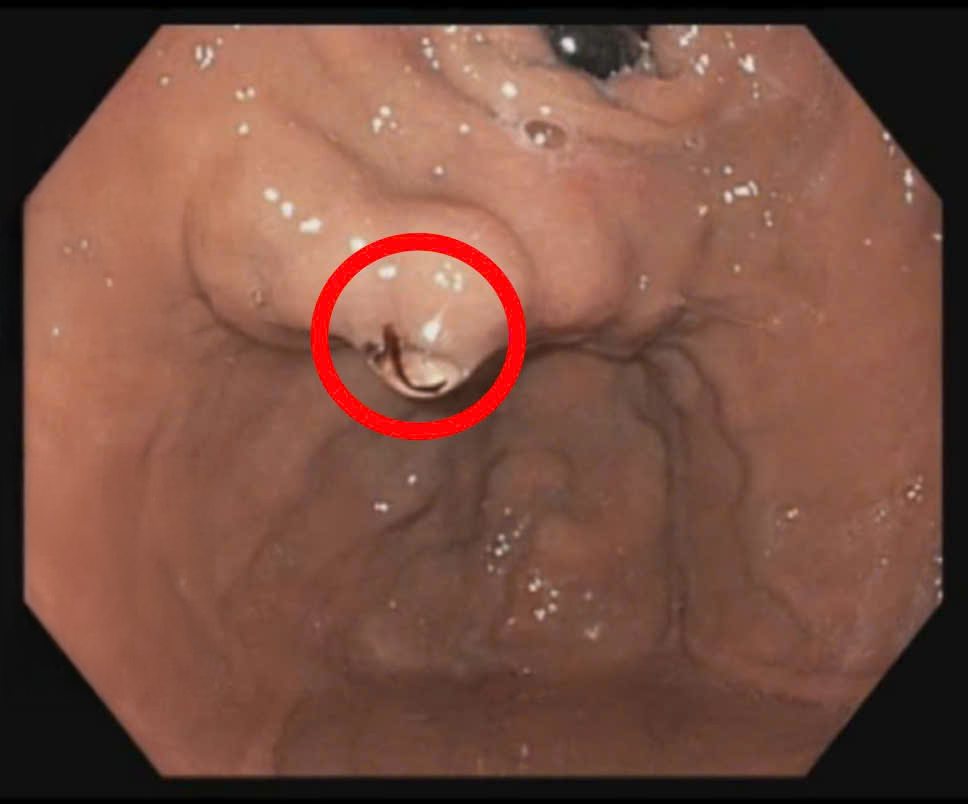

Ngay khi tiếp nhận, các bác sĩ tại Bệnh viện Quốc tế City đã nhanh chóng tiến hành cấp cứu và thực hiện nội soi tiêu hóa để xác định nguyên nhân gây xuất huyết. Kết quả nội soi do BS.CKII. Đinh Đức Minh – bác sĩ Trung tâm Nội soi CIH – Gia An 115 thực hiện cho thấy bệnh nhân bị xuất huyết tiêu hóa trên do vỡ giãn tĩnh mạch phình vị IGV-1, một biến chứng hiếm gặp nhưng cực kỳ nguy hiểm ở bệnh nhân xơ gan. Khi tĩnh mạch phình vị giãn lớn và vỡ, máu có thể chảy ồ ạt vào đường tiêu hóa, gây nguy cơ mất máu nghiêm trọng, dẫn đến sốc, suy đa cơ quan và thậm chí tử vong nếu không được can thiệp kịp thời.

Hình ảnh búi giãn tĩnh mạch ở phình vị IGV-1